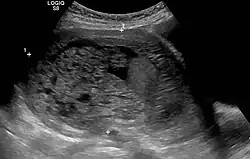

The diagnosis is strongly suggested by ultrasound (sonogram), but definitive diagnosis requires histopathological examination. On ultrasound, the mole resembles a bunch of grapes ("cluster of grapes" or "honeycombed uterus" or "snow-storm").[14] There is increased trophoblast proliferation and enlarging of the chorionic villi, and angiogenesis in the trophoblasts is impaired.[15]